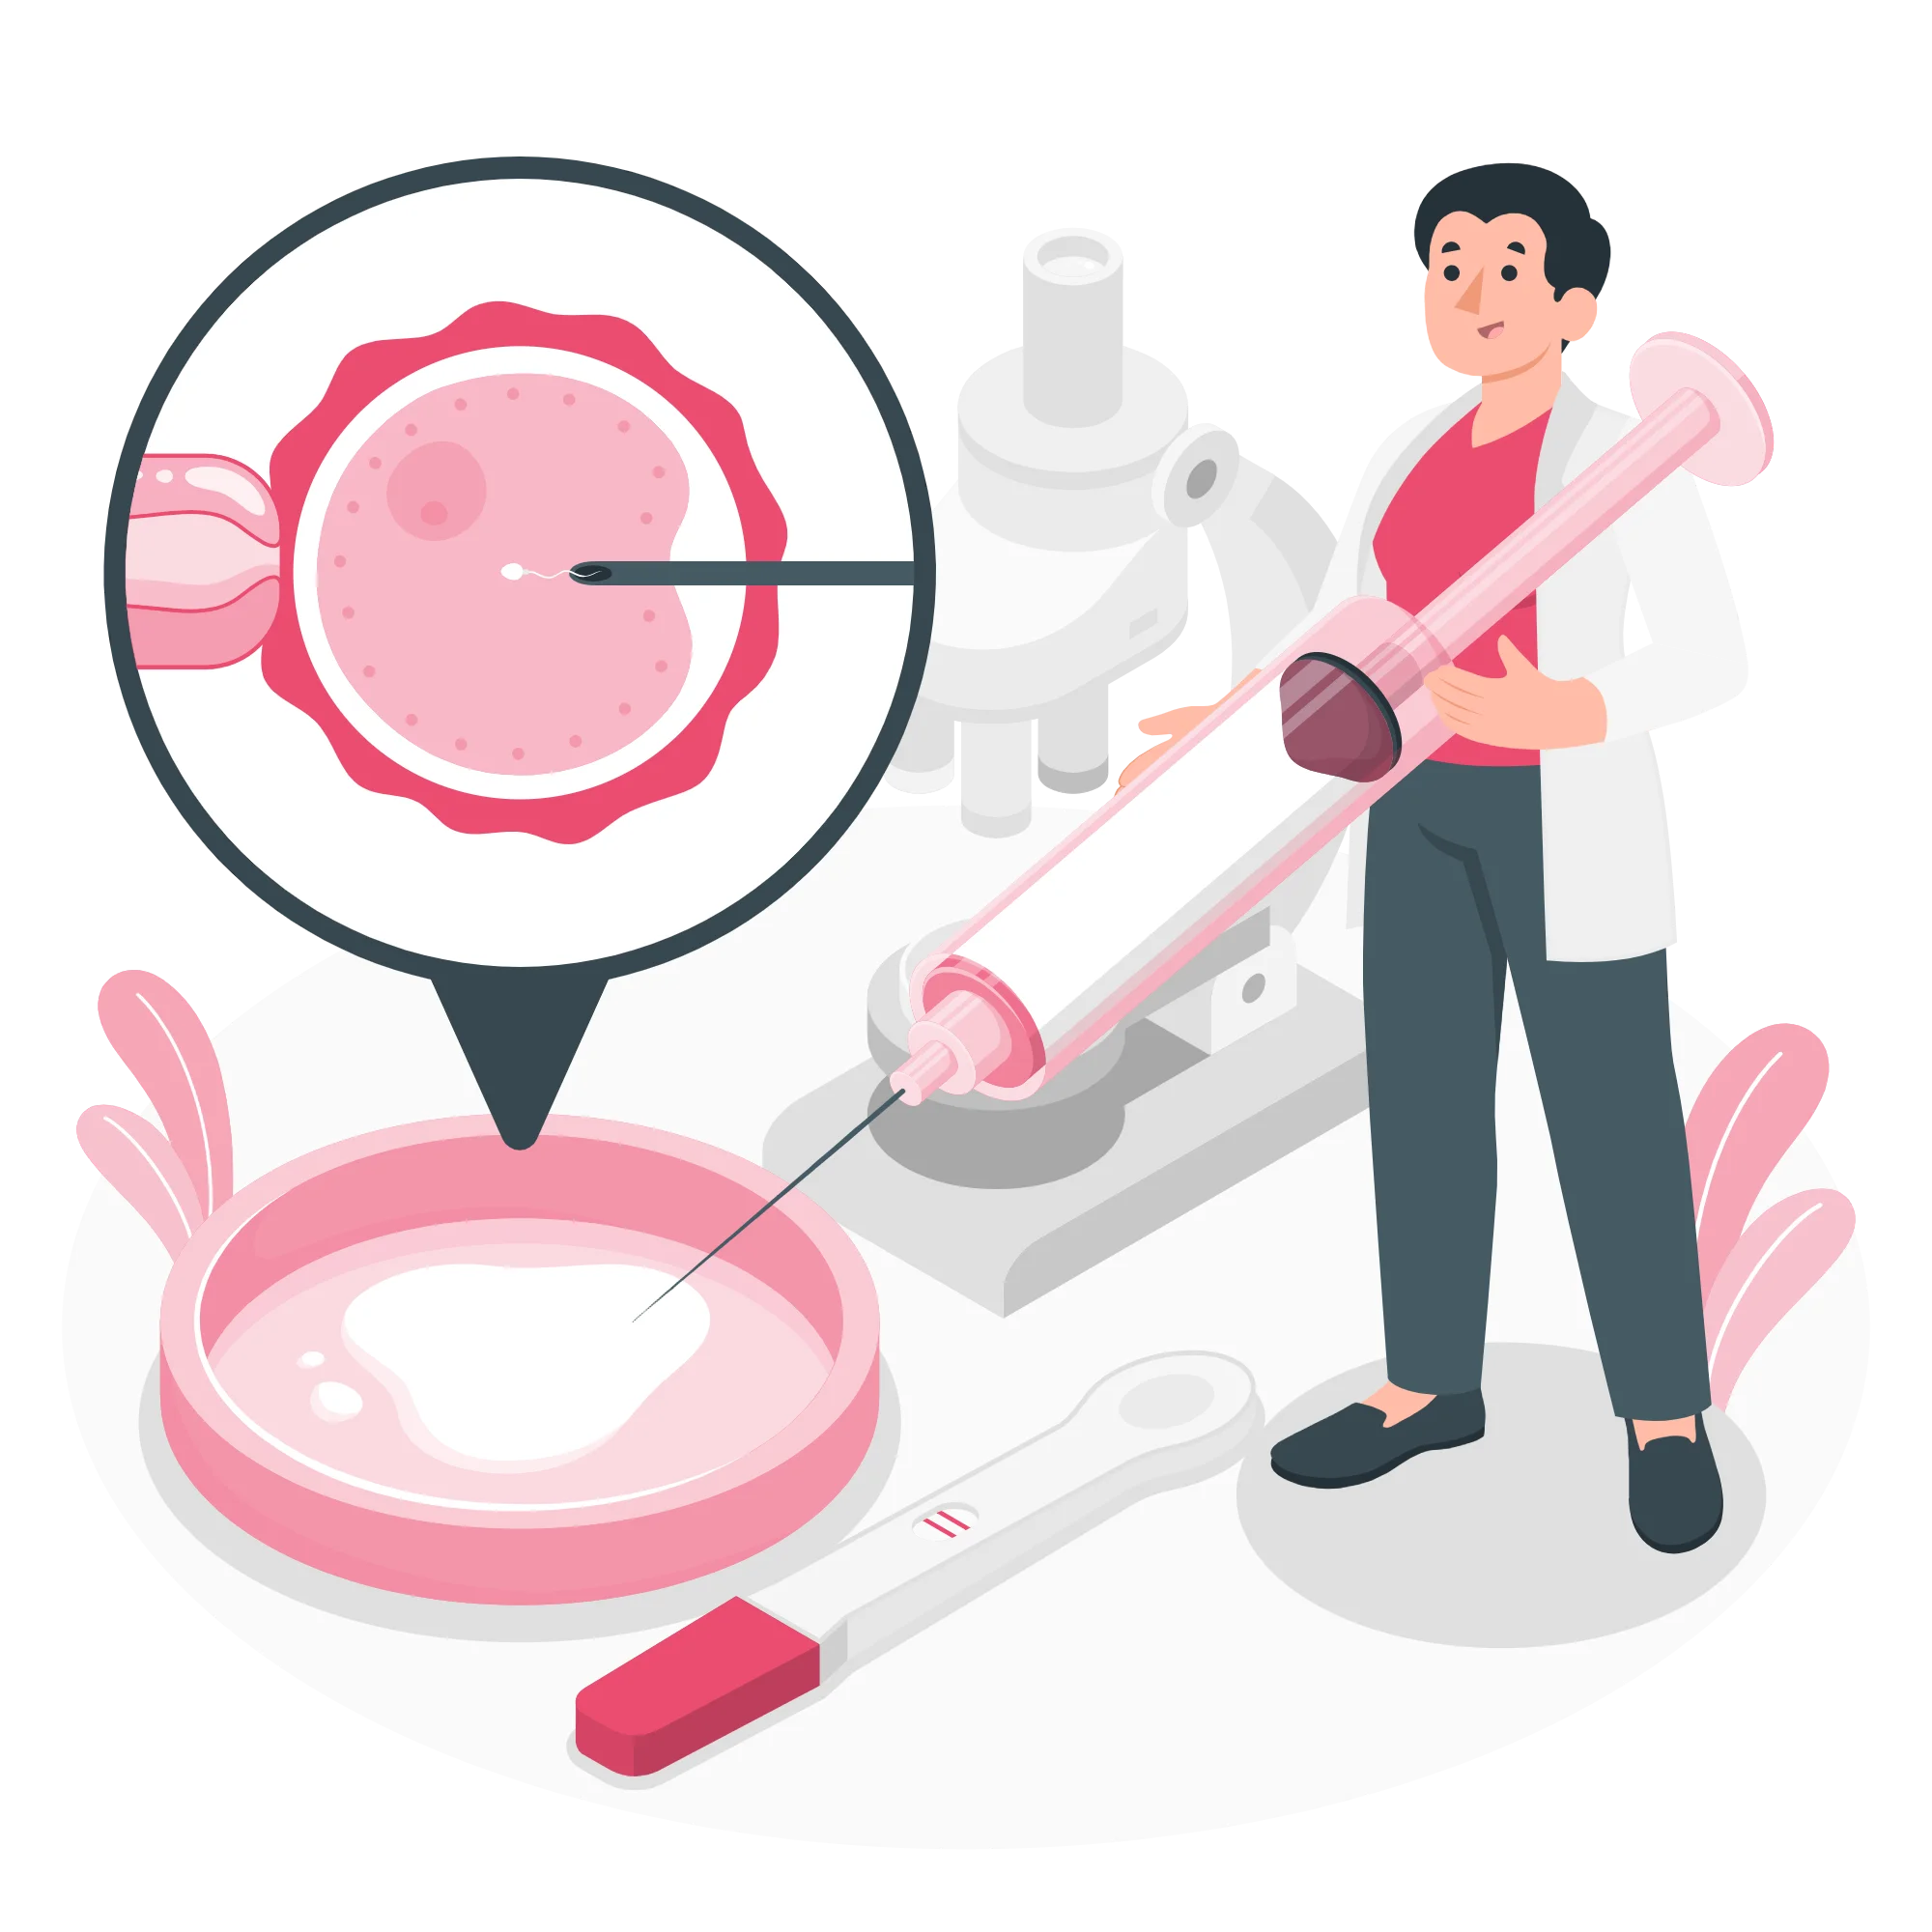

الحقن المجهري

فرص جديدة للحياة والأمل المستمر

![]() تقنية متطورة: نستخدم أحدث تقنيات الحقن المجهري لضمان أعلى معدلات النجاح في علاج العقم بدقة متناهية.

تقنية متطورة: نستخدم أحدث تقنيات الحقن المجهري لضمان أعلى معدلات النجاح في علاج العقم بدقة متناهية.

![]() رعاية شخصية: نوفر دعماً شاملاً لكل حالة مع متابعة مستمرة لتحقيق أفضل النتائج بأمان وراحة.

رعاية شخصية: نوفر دعماً شاملاً لكل حالة مع متابعة مستمرة لتحقيق أفضل النتائج بأمان وراحة.